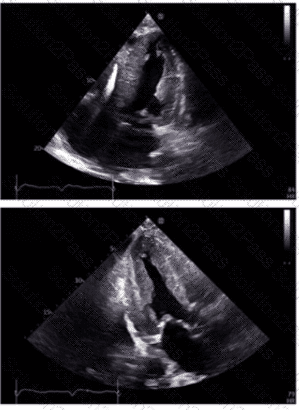

Which diagnosis is most consistent with the findings in these images?